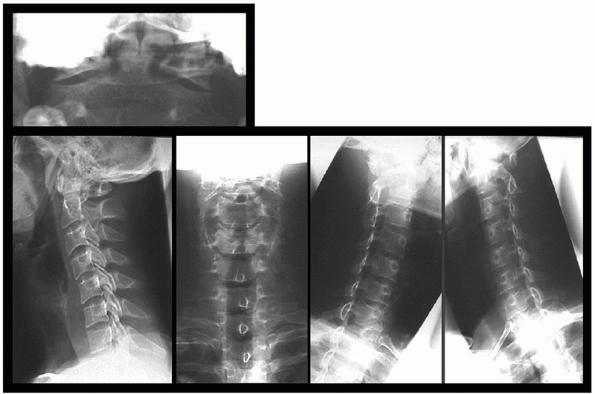

visualization of the cervical spine and include an open-mouth view, are

missing significant fractures is less than 1% of patients.83 The sensitivity of the lateral radiograph alone is 83% and specificity is 97%.173 The addition of open-mouth and AP view increases the sensitivity to approximately 100%.173

Opinions for minimum number of plain radiographs necessary in trauma

flexion-extension) (Figs. 41-6 and 41-7).125

swimmer’s lateral view or a CT scan can visualize this region (Fig. 41-8).

acute injuries. A change in alignment of the uncovertebral joints and

essential for excluding a C1 arch or C2 odontoid process fractures.

open-mouth view in unresponsive patients. Oblique views can identify

particularly at the cervicothoracic junction. For this reason, oblique

cervical radiographs.

![]() |

FIGURE 41-6 Standard radiographs of the cervical spine.

FIGURE 41-7 Flexion-extension radiographs.